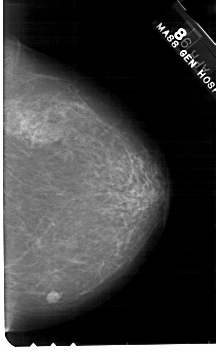

A_1562_1.RIGHT_MLO

RIGHT_MLO LINES 5491 PIXELS_PER_LINE 3211 BITS_PER_PIXEL 12 RESOLUTION 43.5 NON_OVERLAY